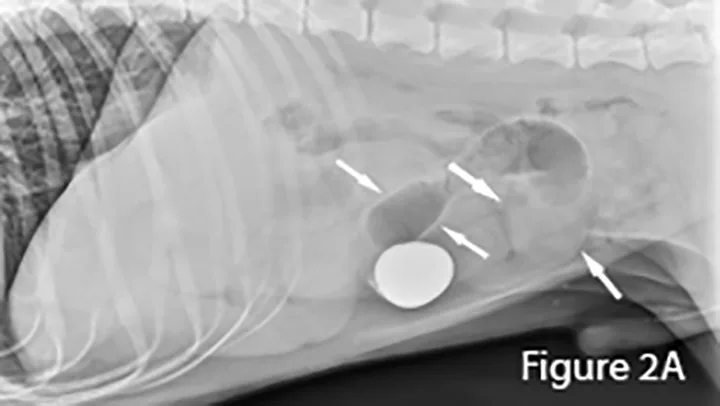

A foreign body (ie, rock) is identifiable in this canine small intestine. The markedly dilated segment of jejunum (arrows) leading up to the foreign body (~4× the height of L5) is significant.

Small intestinal foreign material recognized as heterogeneous soft tissue opacity (arrows). Nearly all the small intestine is abnormally distended, indicating a distal small intestinal obstruction. The colon is empty. Distal small intestinal obstructions caused by radiographically nonopaque material warrants consideration of diffuse functional ileus. Differentiation between mechanical and functional small bowel dilation (eg, parvovirus infection, mesenteric torsion) can be difficult.

Ultrasound of small intestinal foreign material typically appears hyperechoic (small arrows) with strongly distal acoustic shadowing (large arrows), although this can vary depending on composition, shape, and number. Foreign material will not change shape with peristalsis and often has an organized surface for differentiation from intraluminal gas, which typically causes reverberation artifacts (ie, comet tails).